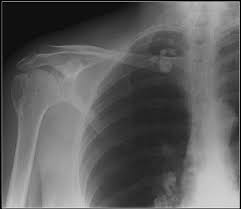

A Radiograph Taken For The Right Shoulder Shows Old Healed Download Scientific Diagram